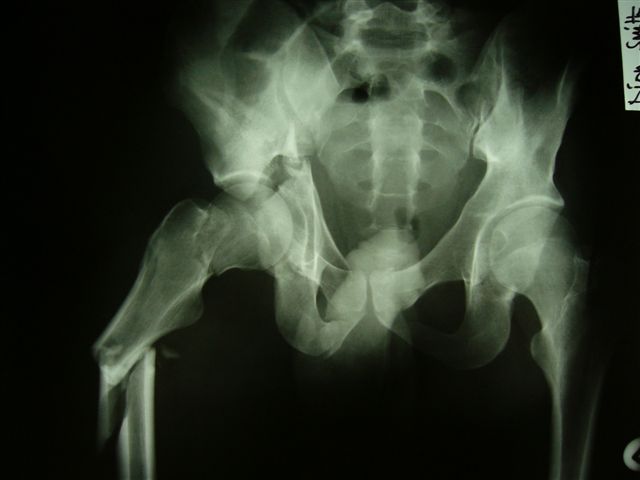

Уважаемые коллеги,Мужчина 36 лет от роду попал в ДТП 24.08.04 Рентгенограммы в приложении.

Диагноз- перелом с вовлечением таза, разрыв правого сакро-илиак сочленения vertical shear injury, перелом крыла подвздошной кости?, перелом ацетабулум Т type или Both column?, перелом шейки бедра, перелом проксимального отдела бедра.

перелом крыла правой подвздошной кости, перелом обеих колонн вертлужной впадины, двусторонний перелом лонных костей (С2.2) повреждение передних связок правого крестцово-подвздошного сочленения,

ипсилатеральный перелом шейки и диафиза бедра.